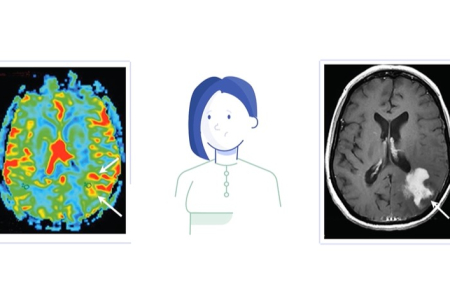

Zaterdag 21 september is het Wereld Alzheimer Dag. Op deze Wereld Alzheimer Dag wordt wereldwijd aandacht gevraagd voor dementie. 1 op de 5 mensen krijgt dementie. Er is onderzoek nodig om dementie uiteindelijk te kunnen stoppen. Ook de radiologie speelt een belangrijke rol in de strijd tegen Alzheimer en andere vormen van dementie. Neuroradiologen zijn betrokken bij twee toonaangevende onderzoeksprojecten in Nederland: ABOARD en TAP-dementia.